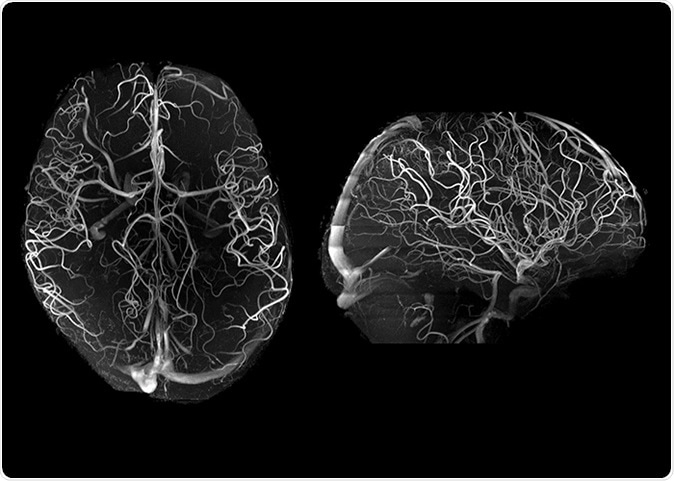

7T angiography in late life depression patients with the “Tic-Tac-Toe” RF coil system and without the use of invasive contrast agents. While not feasible at 3T, 7T super high-resolution acquisitions (voxel size is 0.2 mm in all directions) significantly improve the conspicuity of small arterioles.